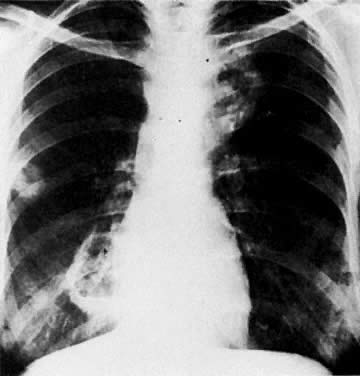

SPREAD TO CHEST

Methods of Spread

Metastatic spread to the chest from gynecologic malignancies is uncommon and occurs predominantly by the hematogenous route. Lymphatic spread is rare.133,134,135 At autopsy, metastatic pulmonary lesions were found in 27.9% of patients with cervical carcinoma,117 30.2% with endometrial carcinoma,117 and 37.2% with ovarian carcinoma (see Table 4).118 In pretreatment chest radiographs, however, the incidence of chest metastases was found to be less than 1% in two separate studies.108,136 Ovarian carcinoma can spread via the peritoneal cavity through the diaphragm into the pleural cavity, causing malignant pleural deposits and effusions.

Radiologic Examinations and Findings

The posteroanterior and lateral chest radiographic examination is a standard procedure in staging gynecologic malignancies. Decubitus views are performed to confirm the presence of free pleural effusion. The side with the suspected effusion is placed in the dependent position; if free fluid is present, it will layer along the lateral chest wall.

Chest CT is a more sensitive and accurate test that can be used to confirm the presence of lesions and to differentiate benign from malignant ones. CT better visualizes lesions in the apices of the lungs, costophrenic sinuses, cardiophrenic angles, mediastinum, and supradiaphragmatic areas. In some cases, pleural-based lesions (Fig. 53) and loss of rib detail are also better demonstrated by CT.137 CT can identify diffuse calcification by assigning a higher number to the nodule. Unfortunately, CT cannot differentiate benign from malignant nodules when they are not calcified. Recent advances in CT technology, including spiral CT, have been used to reconstruct three-dimensional images of the chest and detect tumor spread to the pleura. In addition, spiral CT probably has a higher rate of detection of metastatic nodules than conventional CT, because of the lack of respiratory motion artifacts. CT-guided fine-needle percutaneous aspiration biopsy is used to differentiate benign from malignant chest nodules with a high degree of accuracy.

Fig. 53. A. Posteroanterior chest film with metastatic lesion in left upper lung field, second anterior interspace ( arrow ). B. Axial CT scan shows the lesion ( arrow) projecting from the pleura.